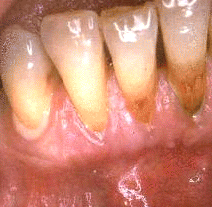

Mujer de 64 años de edad con enfermedad periodontal severa en los dientes antero inferiores. Las profundidades de bolsa al sondaje es de 5 a 8 mm. En el examen inicial se observa sangrado  y  flujo de pus al sondaje suave de la bolsa periodontal. La imagen ilustra el síntoma prominente de la enfermedad periodontal severa.